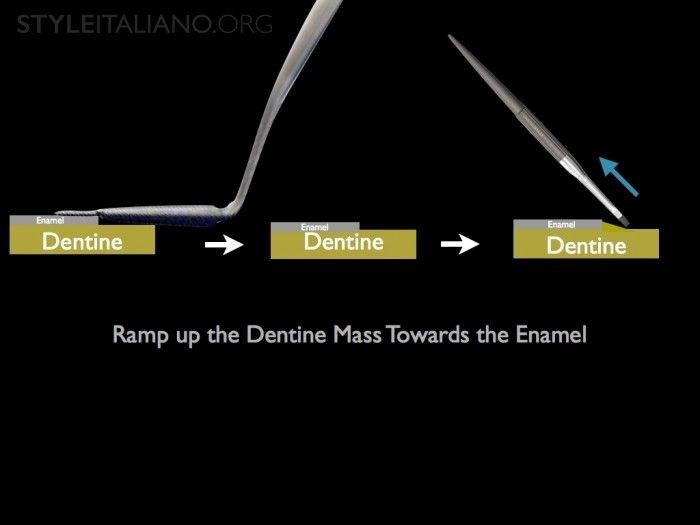

Hình 20. Tip 3. Sau khi lấy bỏ phần composite màu ngà thừa, không nên để bề mặt composite ghồ ghề lởm chởm khi đắp tiếp lớp composite màu men. Tác giả gợi ý sử dụng chổi (cọ) trám phù hợp để vuốt láng phần composite và đẩy composite màu ngà thêm về phía men răng để tạo sự chuyển tiếp. Nhờ đó sẽ giảm sự khác biệt đột ngột về màu sắc giữa miếng trám và mô răng thật.